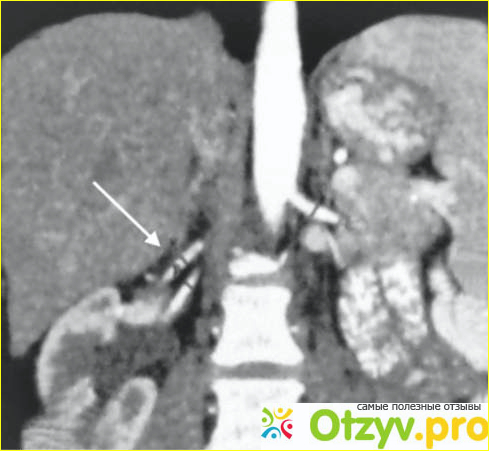

А если у человека нефроптоз, то почка может опускаться даже в брюшную полость. Нарушаются все процессы, и вены и мочеточник претерпевают трудности в функционировании. Очень плохо, что очень долго никаких симптомов вообще не возникает.

Почка уже может сместиться даже в область малого таза. Только представьте себе?!